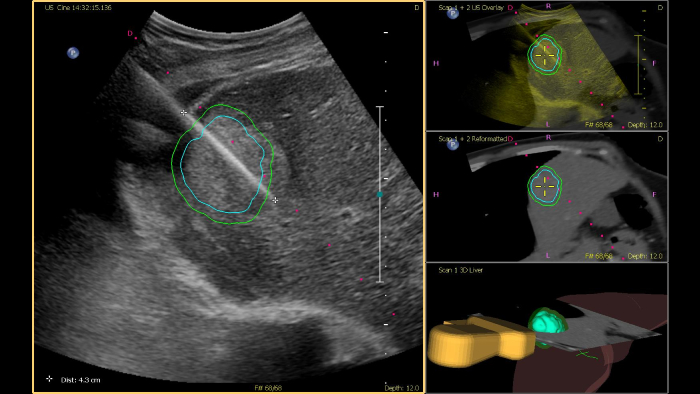

Philips ultrasound systems for interventional radiology support a range of sophisticated capabilities for interventional applications. Streamlined workflow allows clinicians to achieve fast and effective fusion of CT/MR/PET/CBCT with live ultrasound, while needle navigation aids in guiding biopsy and ablation of small and difficult-to-access lesions. Fusion and navigation can also be used in conjunction with Contrast-Enhanced Ultrasound (CEUS), giving clinicians access to even more powerful diagnostic tools with advanced visualization.

The CIVCO Verza biopsy guide can be attached directly to the transducer, without an external bracket, allowing needle guidance with a minimal blind zone. Embedded electromagnetic sensors provide an ergonomic solution for fusion and navigation by not requiring external tracking accessories.

This semi-automated tool helps outline a 3D contour around a structure of interest, improving procedure guidance even in challenging cases where the lesion may not be visually obvious under ultrasound. The lesion can be rendered in 3D or 2D via a complementary modality and overlaid on the live ultrasound or CT, helping visualize the location in relation to surrounding critical structures.